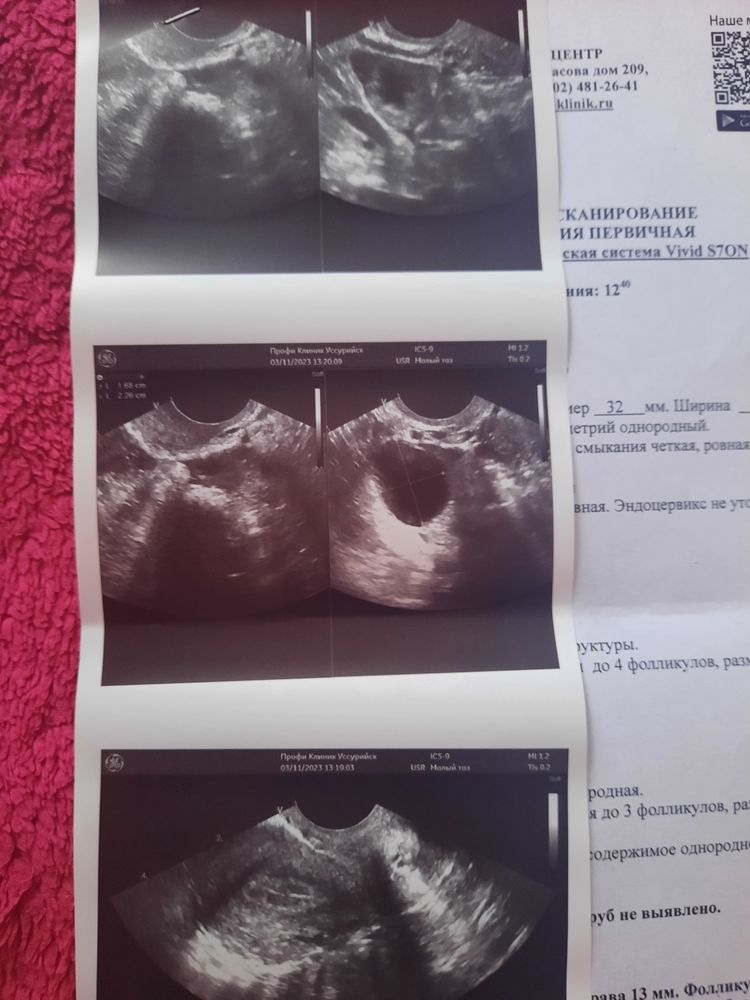

Принимала дюфастон с 16 по 25 дц. Решила сходить на узи фолликулометрию. Т.к после ЗБ, вообще организм себя странно ведёт. И вот такой результат. Фолликулярная киста справа и желтое тело справа, если често не особо понимаю как такое может быть. Сегодня 10 день цикла Т.е возможно, овуляции и не было в этом цикле. Кто сталкивался с подобной ситуацией?

Что такое овуляция- это фолликул, котороый лопнул и из него вышла яйцеклетка. Что такое киста - это фолликул, который не лопнул. Почему вы решили, что это глупость. Росли у вас на одном яичнике 2 доминантных фолликула, один больше, другой поменьше. Во всплеск ЛГ, один лопнул, а второй ещё не был готов, не дозрел. Но т.к всплеск ЛГ происходит 1 раз, меньший доминантный фолликул так и не лопнул , перешёл в кисту. Виола, на одном яичнике киста и жёлтое тело

И желтое тело, и кисту одновременно увидел? Звучит как фантастика (или некомпетентность).

Герда, вот и я удивилась, как такое может быть

Это само узи, вот и гадаю, это киста или желтое тело

Ява, на кисту больше похоже желтого тела, у меня такая же просто похожая была. Советую повторно сходить, что бы по смотрели к другому узисту